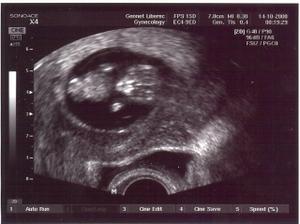

14.10.08 poradna - odebrána krev+moč-výsledky za 14dní, mimísek má 4cm a dostali jsme TĚHOTENSKOU PRŮKAZKU🙂)).............................................27.10.08 poradna - mimísek má 6,5cm, genetický test v naprostém pořádku, riziko se snížilo na 1/9050 - takže téměř žádné-huráááááááá!............................................. 19.11.2008 odběry krve na triplle testy v 16tt - negativní🙂))............................................. 16.12.2008 poradna - vše v pořádku.............................................18.12.2008 velký ultrazvuk - mimísek je v naprostým pořádku, srdčko i všechno ostatní funguje jek má🙂)))............................................. 13.1.2009 poradna + test na cukr............................................. 27.1.2009 poradna - cokrovka je negativní, můžeme mlsat dál🙂............................................. 13.2.2009 4D ultrazvuk-mimísek se nám pořád skovával za ručičky, ale nakonec jsme ho přemluvili a aspoň na chvilku se nám ukázal🙂)............................................. 17.2.2009 poradna- prcek už je hlavičkou dolů a připravenej jít ven, navíc mi strašně tvrdne břicho takže mi dr. zvýšil dávku magnézia a musíme ležet............................................. 2.3.2009 velký ultrazvuk v 31tt - prcek je v pořádku a už má 1700g ............................................. 17.3.2009 poradna - vše ok, prcek má 2100g ............................................. 18.3.2009 sepsání porodopisu ............................................. 26.3.2009 nástup na mateřskou🙂